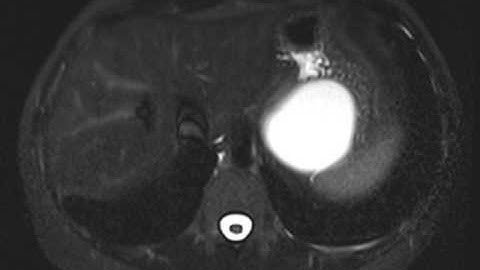

Gastric Duplication Cyst with Cinematic Rendering